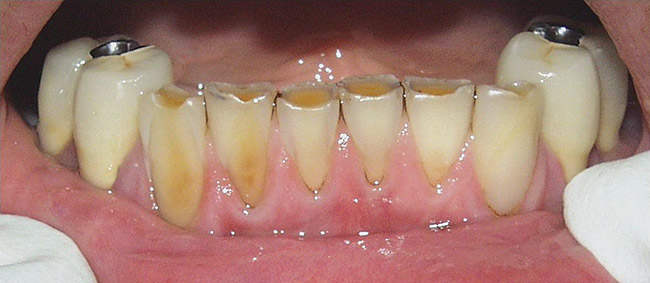

Figure  2  Loss of tooth surface surrounding amalgam and appearance of the restoration protruding from the tooth surface.

Figure 2

Figure  3  Severe dental erosion and attrition in a GERD patient.

Figure 3